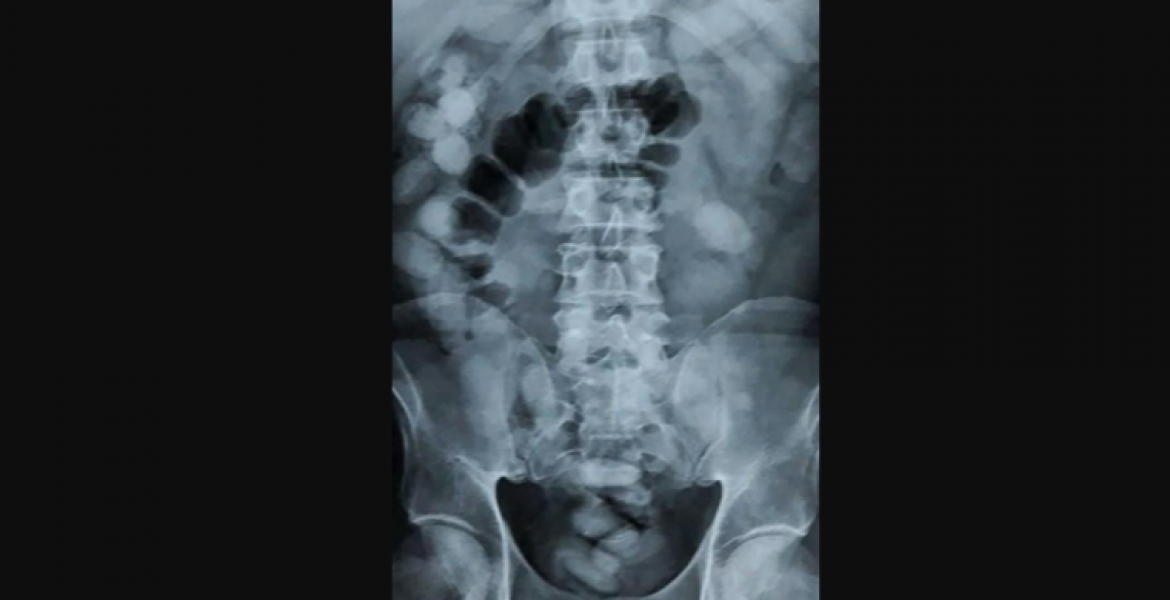

“An x-ray showed she had swallowed 1.2kg of cocaine in a bid to avoid detection,” Niyom Termsrisuk, a Thai official said.